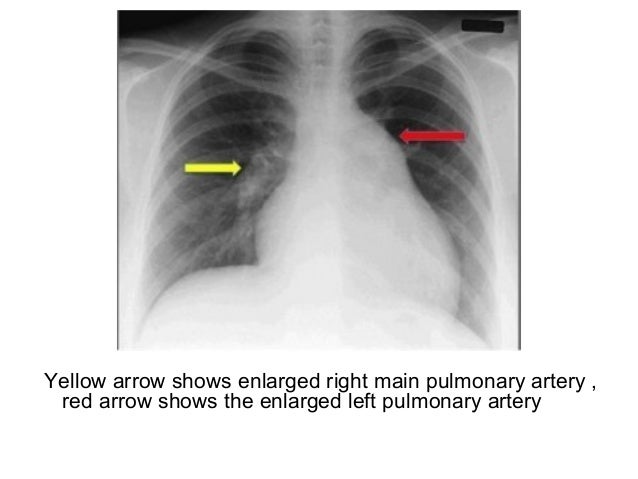

A Chest Radiograph Shows A Markedly Enlarged Pulmonary Trunk Red Download Scientific Diagram

Chest X Ray Cardiomegaly Involving Right Chambers Enlarged Pulmonary Download Scientific Diagram